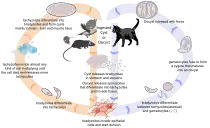

Life cycle

The life cycle of T. gondii may be broadly summarized into two components: a sexual component that occurs only within cats (felids, wild or domestic), and an asexual component that can occur within virtually all warm-blooded animals, including humans, cats, and birds.[28]: 2 Because T. gondii can sexually reproduce only within cats, cats are therefore the definitive host of T. gondii. All other hosts – in which only asexual reproduction can occur – are intermediate hosts.

Sexual reproduction in the feline definitive host

When a feline is infected with T. gondii (e.g. by consuming an infected mouse carrying the parasite's tissue cysts), the parasite survives passage through the stomach, eventually infecting epithelial cells of the cat's small intestine.[28]: 39 Inside these intestinal cells, the parasites undergo sexual development and reproduction, producing millions of thick-walled, zygote-containing cysts known as oocysts. Felines are the only definitive host because they lack expression of the enzyme delta-6-desaturase (D6D) in their intestine. This enzyme converts linoleic acid; the absence of expression allows systemic linoleic acid accumulation. Recent findings showed that this excess of linoleic acid is essential for T. gondii sexual reproduction.[6]

Feline shedding of oocysts

Infected epithelial cells eventually rupture and release oocysts into the intestinal lumen, whereupon they are shed in the cat's feces.[4]: 22 Oocysts can then spread to soil, water, food, or anything potentially contaminated with the feces. Highly resilient, oocysts can survive and remain infective for many months in cold and dry climates.[29]

Ingestion of oocysts by humans or other warm-blooded animals is one of the common routes of infection.[30] Humans can be exposed to oocysts by, for example, consuming unwashed vegetables or contaminated water, or by handling the feces (litter) of an infected cat.[28]: 2 [31] Although cats can also be infected by ingesting oocysts, they are much less sensitive to oocyst infection than are intermediate hosts.[32][4]: 107

Initial infection of the intermediate host

Intermediate hosts found include pigs, chickens, goats, sheep[28]: 2 and Macropus rufus by Moré et al. 2010.[33]: 162 Cattle and horses are resistant and thought to be incapable of significant infection.[28]: 11 T. gondii is considered to have three stages of infection; the tachyzoite stage of rapid division, the bradyzoite stage of slow division within tissue cysts, and the oocyst environmental stage.[34] Tachyzoites are also known as "tachyzoic merozoites" and bradyzoites as "bradyzoic merozoites".[35] When an oocyst or tissue cyst is ingested by a human or other warm-blooded animal, the resilient cyst wall is dissolved by proteolytic enzymes in the stomach and small intestine, freeing sporozoites from within the oocyst.[30][34] The parasites first invade cells in and surrounding the intestinal epithelium, and inside these cells, the parasites differentiate into tachyzoites, the motile and quickly multiplying cellular stage of T. gondii.[28]: 39 Tissue cysts in tissues such as brain and muscle tissue, form about 7–10 days after initial infection.[34] Although severe infection of M. rufus has been observed it is unknown whether this is common.[33]

Asexual reproduction in the intermediate host

Inside host cells, the tachyzoites replicate inside specialized vacuoles (called the parasitophorous vacuoles) created from host cell membrane during invasion into the cell.[28]: 23–39 Tachyzoites multiply inside this vacuole until the host cell dies and ruptures, releasing and spreading the tachyzoites via the bloodstream to all organs and tissues of the body, including the brain.[28]: 39–40

Formation of tissue cysts

Following the initial period of infection characterized by tachyzoite proliferation throughout the body, pressure from the host's immune system causes T. gondii tachyzoites to convert into bradyzoites, the semidormant, slowly dividing cellular stage of the parasite.[36] Inside host cells, clusters of these bradyzoites are known as tissue cysts. The cyst wall is formed by the parasitophorous vacuole membrane.[28]: 343 Although bradyzoite-containing tissue cysts can form in virtually any organ, tissue cysts predominantly form and persist in the brain, the eyes, and striated muscle (including the heart).[28]: 343 However, specific tissue tropisms can vary between intermediate host species; in pigs, the majority of tissue cysts are found in muscle tissue, whereas in mice, the majority of cysts are found in the brain.[28]: 41

Consumption of tissue cysts in meat is one of the primary means of T. gondii infection, both for humans and for meat-eating, warm-blooded animals.[28]: 3 Humans consume tissue cysts when eating raw or undercooked meat (particularly pork and lamb).[39] Tissue cyst consumption is also the primary means by which cats are infected.[4]: 46

Chronic infection

Tissue cysts can be maintained in host tissue for the lifetime of the animal.[28]: 580 However, the perpetual presence of cysts appears to be due to a periodic process of cyst rupturing and re-encysting, rather than a perpetual lifespan of individual cysts or bradyzoites.[28]: 580 At any given time in a chronically infected host, a very small percentage of cysts are rupturing,[28]: 45 although the exact cause of this tissue cyst rupture is, as of 2010, not yet known.[4]: 47

Theoretically, T. gondii can be passed between intermediate hosts indefinitely via a cycle of consumption of tissue cysts in meat. However, the parasite's life cycle begins and completes only when the parasite is passed to a feline host, the only host within which the parasite can again undergo sexual development and reproduction.[30]

Merozoites

Like tachyzoites, merozoites divide quickly, and are responsible for expanding the population of the parasite inside the cat's intestine before sexual reproduction.[28]: 19 When a feline definitive host consumes a tissue cyst (containing bradyzoites), bradyzoites convert into merozoites inside intestinal epithelial cells. Following a brief period of rapid population growth in the intestinal epithelium, merozoites convert into the noninfectious sexual stages of the parasite to undergo sexual reproduction, eventually resulting in zygote-containing oocysts.[28]: 306

Bradyzoites

Bradyzoites are the slowly dividing stage of the parasite that make up tissue cysts. When an uninfected host consumes a tissue cyst, bradyzoites released from the cyst infect intestinal epithelial cells before converting to the proliferative tachyzoite stage.[28]: 359 Following the initial period of proliferation throughout the host body, tachyzoites then convert back to bradyzoites, which reproduce inside host cells to form tissue cysts in the new host.

Sporozoites

Sporozoites are the stage of the parasite residing within oocysts. When a human or other warm-blooded host consumes an oocyst, sporozoites are released from it, infecting epithelial cells before converting to the proliferative tachyzoite stage.[28]: 359